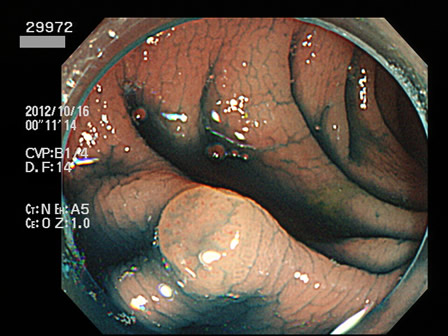

29901 29904 29905 29906 29907 29908 29909 29913 29915 29917 29918 29921 29925 29926 29927 29928 29930 29934 29936 29938 29939 29940 29941 29942 29943 29944 29945 29947 29948 29949 29955 29959 29961 29962 29965 29968 29972 29975 29979 29980 29981 29983 29985 29986 29987 29989 29993 29996 29998 29999・・・・・・・の50名

上記100名より抽出した平坦・陥凹型腺腫(=癌化の危険が高いが見落としやすい病変)の内視鏡写真